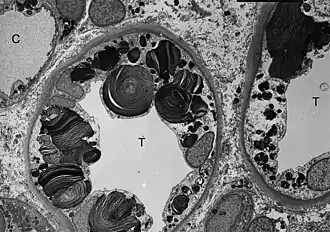

![]() ТЭМ-микроскопия показывает наличие включений гликосфинголипидов различной формы и размеров в клетках дистальных канальцев почки. | |